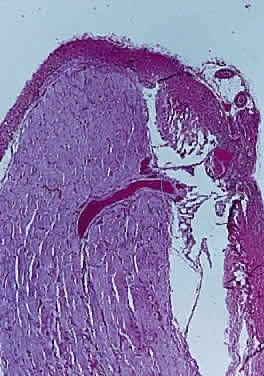

Hypoplasia of the optic nerve is also rare but is more common than aplasia (Figs. 13 and 14). It represents one of the most important developmental abnormalities of the eye and is increasingly recognized as a significant cause of visual deficit in children. Congenital nerve hypoplasia is a nonprogressive condition associated with a reduction in the number of retinal ganglion cells and axons. It may be either unilateral or more commonly bilateral and may involve the entire nerve or be segmental. Although a hypoplastic optic nerve is usually idiopathic, an increased incidence has been noted in the offspring of diabetic mothers and with the maternal use of phenytoin, quinine and, alcohol. Rare reports of an inherited disorder may be found in the literature. Although it may be an isolated abnormality, the hypoplasia is frequently associated with other anomalies—both ocular and nonocular. Additional ocular abnormalities include microphthalmos and congenital nonattachment of the retina. The most common nonocular abnormalities associated with congenital optic nerve hypoplasia include midline CNS structural defects, including septo-optic dysplasia of the septum and ectropia of the posterior pituitary, producing diabetes insipidus.

Fig. 13. Hypoplasia of optic nerve (hematoxylin and eosin staining). Note lack of formation of optic disc tissue.

In optic nerve hypoplasia, the optic disc appears gray and is about half its normal size but retinal vessels are present because the optic stalk is invaginated by mesoderm. The optic foramen is also small. Clinically, there may be strabismus, nystagmus, and decreased visual acuity. Severe cerebral abnormalities may be present but the hypoplastic nerve may be the sole abnormality.